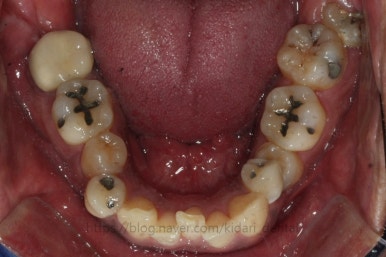

드디어 치료 종료시의 모습입니다. 2년 4개월 걸렸네요.

앞니 안쪽에는 유지철사를 붙여주었고요. 임플란트가 필요한 부위랑 맞닿은 부분은 치열이 움직이지 않도록 철사로 잡아주었어요.(오른쪽 어금니 부위)

삐뚤었던 치아들이 가지런해졌습니다.

왼쪽 송곳니를 발치했지만 별로 표시가 안나게 마무리를 했습니다.

많이 썩은 치아들은 다 뽑았고, 틈새도 다 다물어졌습니다.

원래 패여 있던 부위는 완벽하게 만들기는 힘들지만 앞으로 관리를 잘해주시면 이 모습 그대로 오래 사용하실 수 있으실거에요.